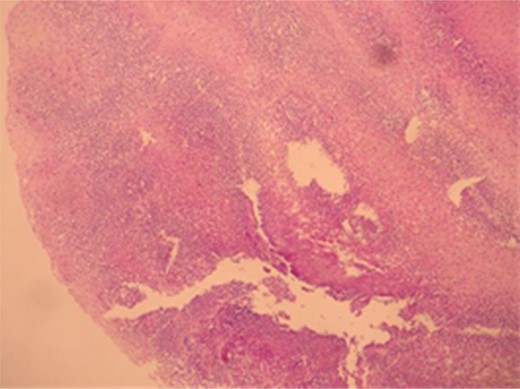

A male patient of 35 years age presented to our General Surgery Clinic with complaints of difficulty in swallowing, sensation of food sticking in the back of the breast while eating, stomach ache, weight loss and weakness for nearly a year. The fact that the symptoms chiefly arose upon ingestion of dairy products was interesting. Normal values were obtained for complete blood count serum CRP, sedimentation and total serum IgE of the patient. Standing abdominal X-ray and abdominal ultrasonography failed to reveal any evidence of pathology. Mucosal fissure and erosional areas were observed in the middle distal esophagus using upper GI endoscopy and are probably associated with reflux esophagitis; biopsies were made of the same (Fig. 1). Bulbitis and pangastritis were observed in the duodenum and stomach and biopsies were made. Pathological examinations of the endoscopic biopsies revealed evidence of chronic esophagitis in esophagus, chronic Helicobacter pylori-positive pangastritis in stomach and chronic duodenitis in the duodenum. The examination showed eosinophilic infiltration only in the esophagus (Fig. 2). Histological examination (40 X) revealed more than 30 eosinophils per field (Fig. 3). The patient was diagnosed with eosinophilic esophagitis and administered dexamethasone I.M as well as treatment for H. pylori eradication which resulted in relief of the symptoms. The patient was also instructed to avoid consumption of milk and dairy products, which caused the development of symptoms. The control endoscopic examination and pathological evaluation made after 3 months, failed to reveal evidence of esophageal eosinophilic infiltration, relapse did not occur during the following 2 years.